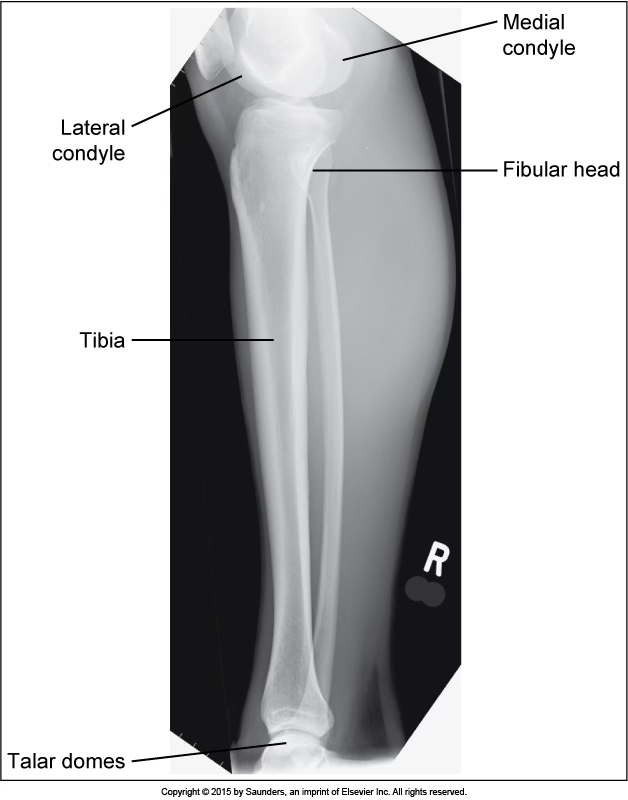

AP tibfib

accurate positioning